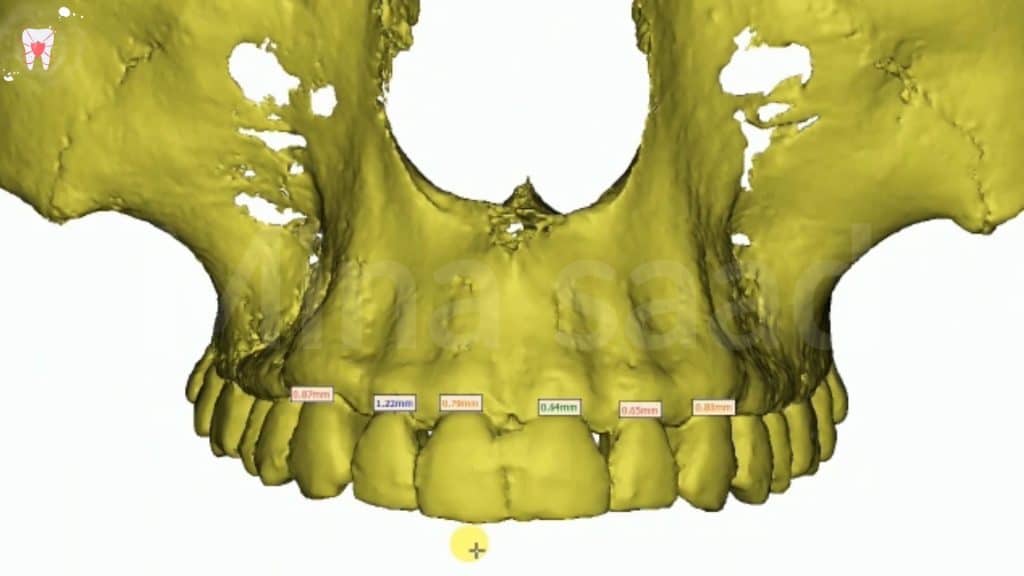

B-CBCT to accurately determine the biologic space available & calculate the needed sufficient space.

“it can be done on CBCT software either in:

A-frontal 3d view. Or B- sagittal view

-Prominence of canine eminence of the right side was observed to more bulky than the left one . “this was confirmed clinically & radiographicaly in occlusal view of CBCT”